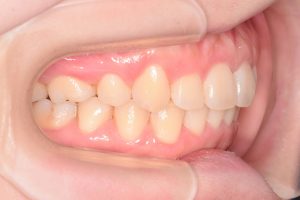

初診時(2022年9月)と装置撤去時(2025年9月)の写真です。

右側

0000000009

0000000137

左側

0000000010

0000000138

まずシザーズバイトを治すのが

非常に難しそうな症例でした。

上顎にリンガルアーチ

下顎にWアーチ

を装着して半年かけて

シザーズバイトを改善させました。

その後も

上の前歯は2.0mm圧下、4.0mm後退

させる計画ということで時間を要しましたが

ギリギリ3年を切って終了できました。